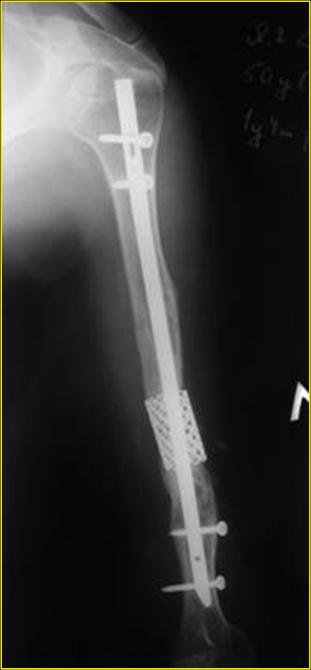

Рентгеновская версия реконструкции. хронология:

после операции, 2 мес. после операции, через 1 год

Движения в полном объеме восстановлены к 2 мес. после операции. Если надо могу показать мультик. Сейчас уже прошло более 3 лет, больная не

показывается. Успехов ЛАФ.